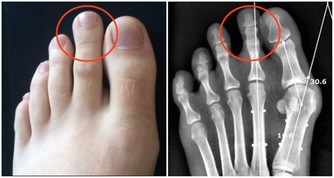

肉類含有大量嘌呤和嘌呤前體,它們在體內可以代謝、轉變為大量尿酸。

人體中的尿酸,大多數是通過腎臟排出來的。所以,體內尿酸太多,腎臟的負擔勢必加重。

若體內尿酸太多,形成結晶鹽,沉積在腎臟,腎臟長期處在慢性炎症的刺激中,便會功能下降。

腎臟功能一旦受損,排泄廢物(包括尿酸)的能力下降,反過來又會使尿酸水平進一步升高,腎功能進一步受損,形成惡性循環。

不僅如此,沉積的尿酸還可能形成結石,誘發腎絞痛、血尿、腎盂腎炎等。較大的腎結石還可能形成梗阻、腎積水,進一步損傷腎功能。